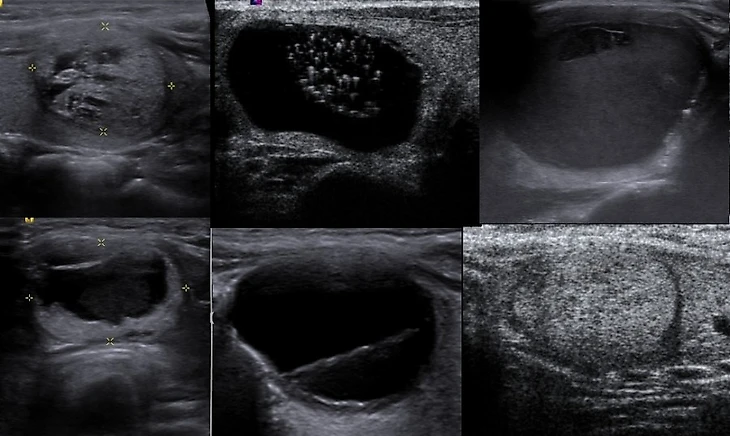

Проблема болезней щитовидки в том, что зачастую мы не понимаем, что «болит» именно она. Симптомы заболевания запросто отнести к чему-нибудь другому или вовсе проигнорировать. Повышенная утомляемость, слабость, плаксивость, резкие перепады настроения, сонливость, выпадение волос, пониженное либидо, отеки, кашель, увеличение или снижение массы тела, сбои в работе сердечно-сосудистой системы, проблемы с циклом у девочек[2]…Никогда не будет такого, что заболит щитовидка и вы это сразу поймете. Как правило, если присутствует что-то из перечисленных симптомов и явной причины для этого нет, то терапевт сразу направляет к эндокринологу. Диагностировать заболевание можно серией простых анализов крови (на ТТГ, иногда назначают также Т3, Т4, на антитела), посредством УЗИ и пунктирования, если на УЗИ видны крупные узлы.